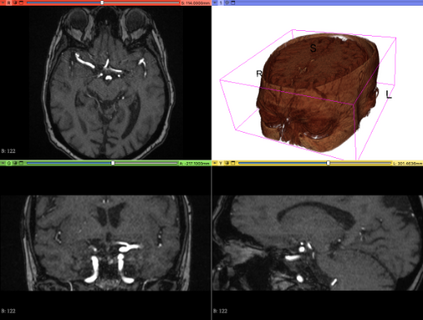

We hereby present a full synthetic model, able to mimic the various constituents of the cerebral vascular tree: the cerebral arteries, the bifurcations and the intracranial aneurysms. By building this model, our goal was to provide a substantial dataset of brain arteries which could be used by a 3D Convolutional Neural Network (CNN) to either segment or detect/recognize various vascular diseases (such as artery dissection/thrombosis) or even some portions of the cerebral vasculature, such as the bifurcations or aneurysms. In this study, we will particularly focus on Intra-Cranial Aneurysm (ICA) detection and segmentation. The cerebral aneurysms most often occur on a particular structure of the vascular tree named the Circle of Willis. Various studies have been conducted to detect and monitor the ICAs and those based on Deep Learning (DL) achieve the best performances. Specifically, in this work, we propose a full synthetic 3D model able to mimic the brain vasculature as acquired by Magnetic Resonance Angiography (MRA), and more particularly the Time Of Flight (TOF) principle. Among the various MRI modalities, the MRA-TOF allows to have a relatively good rendering of the blood vessels and is non-invasive (no contrast liquid injection). Our model has been designed to simultaneously mimic the arteries geometry, the ICA shape and the background noise. The geometry of the vascular tree is modeled thanks to an interpolation with 3D Spline functions, and the statistical properties of the background MRI noise is collected from MRA acquisitions and reproduced within the model. In this work, we thoroughly describe the synthetic vasculature model, we build up a neural network designed for ICA segmentation and detection, and finally, we carry out an in-depth evaluation of the performance gap gained thanks to the synthetic model data augmentation.